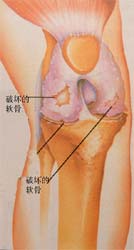

人工关节置换术只是将已磨损破坏的关节面切除,使其恢复正常平滑的关节面。人工关节多由合金,耐磨损的聚乙烯制成。

手术示意图:切除磨损破坏的关节面,安装平滑的 合金关节面和耐磨损的聚乙烯垫

骨性关节炎关节软骨破坏,股骨头坏死 股骨颈骨折,容易发生不愈合